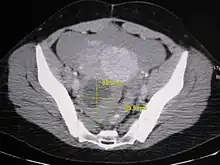

Imaging

Further work up involves imaging, such as a pelvic ultrasound or CT scan.[7] Theca lutein cysts with diameters over 6 cm in size can be seen through these imaging modalities.[18] Benign ovarian cysts and complex cysts that are potentially malignant are distinguishable via ultrasounds.[19] Labs are also collected to evaluate leukocytes and tumor markers, such as beta-hCG and cancer antigen 125 (CA125).[20]

During pregnancy, ultrasonography is the first-line method for evaluating ovarian cysts. Both transabdominal and transvaginal route of ultrasonography are used with either two-dimensional or three-dimensional modalities.[3] Two-dimensional is more common, but three-dimensional can offer more results.[3] Doppler ultrasonography can also be used and is helpful at analyzing the characteristics of the cyst.[3] It can identify the presence of color flow within a septum as well as the presence of a solid component of the mass.[3] Ultrasonography is an effective tool for observing the progression or regression of the cyst.[3] Magnetic resonance imaging (MRI) is the second-line method used when ultrasonography cannot detect the cyst.[3] Cysts that are too large to be accurately analyzed by ultrasonography are typically when MRI would be used.[3] The advantages of MRI are its larger field of view and multiplanar capabilities.[21] In addition, pathologies such as infarctions and placental invasive disorders can be seen more clearly.[3] MRI is especially beneficial in gestational age and obese people.[3] MRI is also beneficial at preventing the exposure of ionizing radiation to the fetus during pregnancy.[22] Both ultrasonography and MRI show enlarged ovaries with multiple theca lutein cysts.[3]